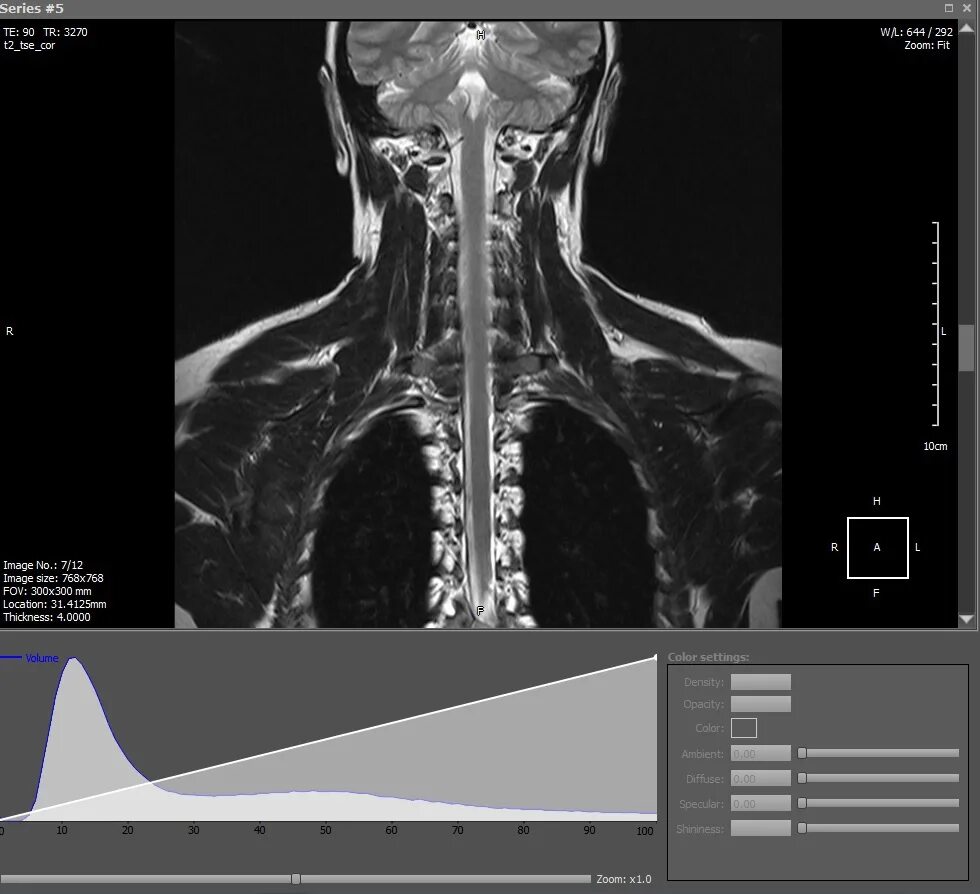

Диск для кт и мрт